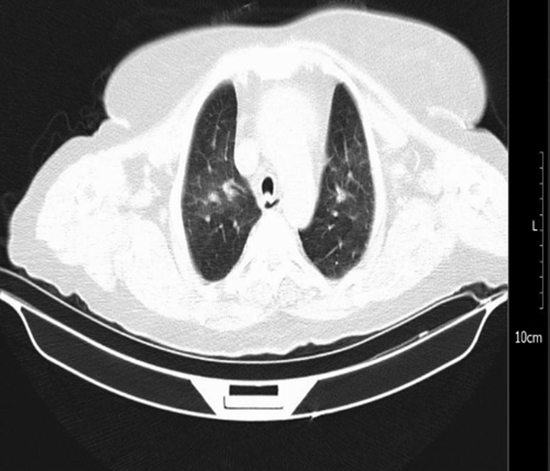

در ابتدا تصور شد که او دچار "لخته خون در ورید گردن" شده و برای درمانش داروی رقیق‌کننده‌ی خون (هپارین) تجویز گردید. اما پس از چند ساعت حال او وخیم‌تر شد و مشخص گردید که علت اصلی بیماری، تجمع مایع در اطراف قلب است — حالتی خطرناک به نام «افیوژن پریکاردی» یا «تامپوناد قلبی». در واقع، تزریق داروی رقیق‌کننده خون باعث تشدید خونریزی دور قلب شده بود و اگر پزشکان به‌موقع عمل نمی‌کردند، می‌توانست منجر به شوک و مرگ شود.

پزشکان با عمل جراحی اورژانسی، حدود یک لیتر خون از اطراف قلب بیمار خارج کردند و او به‌خوبی از عمل نجات یافت. بررسی‌های بعدی نشان داد که این وضعیت احتمالا به‌دلیل التهاب و عفونت ناشی از ویروس کرونا ایجاد شده بود. نکته مهم این بود که بیمار هیچ علامت معمولی از کرونا (مثل تب یا سرفه) نداشت، اما ویروس باعث التهاب در پرده قلب شده بود.

در دوران همه‌گیری‌ها یا عفونت‌های ویروسی، گاهی بیماری‌ها چهره‌ای متفاوت دارند و ممکن است با علائم بیماری‌های دیگر اشتباه شوند. در این مورد، تورم گردن ناشی از فشار مایع اطراف قلب، به‌اشتباه به‌عنوان لخته خون در رگ گردن تعبیر شده بود. بنابراین، محققان تاکید می‌کنند پیش از تجویز داروهای رقیق‌کننده خون باید از تشخیص خود اطمینان کافی داشت، زیرا در مواردی مانند این، درمان اشتباه می‌تواند خطرناک‌تر از خود بیماری باشد. همچنین انجام تصویربرداری‌های دقیق مانند سی‌تی‌اسکن و اکوکاردیوگرافی می‌تواند در تشخیص درست و نجات جان بیمار نقش حیاتی داشته باشد.